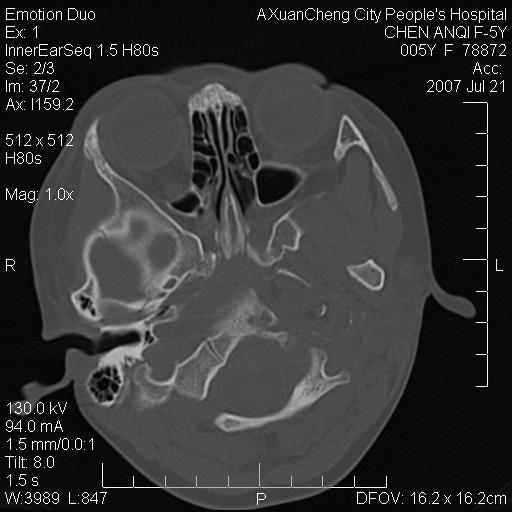

标题: PED0273:5岁,左耳流脓痛疼一周,颅底骨质破坏 [打印本页]

标题: PED0273:5岁,左耳流脓痛疼一周,颅底骨质破坏

患儿5岁,左耳流脓痛疼一周,左外耳道肉芽组织填塞 软组织窗显示病灶内结节状低密度影为气体密度

考虑中耳乳突炎并胆脂瘤形成可能。

左侧中耳炎并胆脂瘤,左颞骨岩部骨质破坏并颅内感染积气。

考虑化脓性中耳乳突炎伴胆脂肪瘤形成并左颞叶感染,不除外合并嗜酸性肉芽肿.